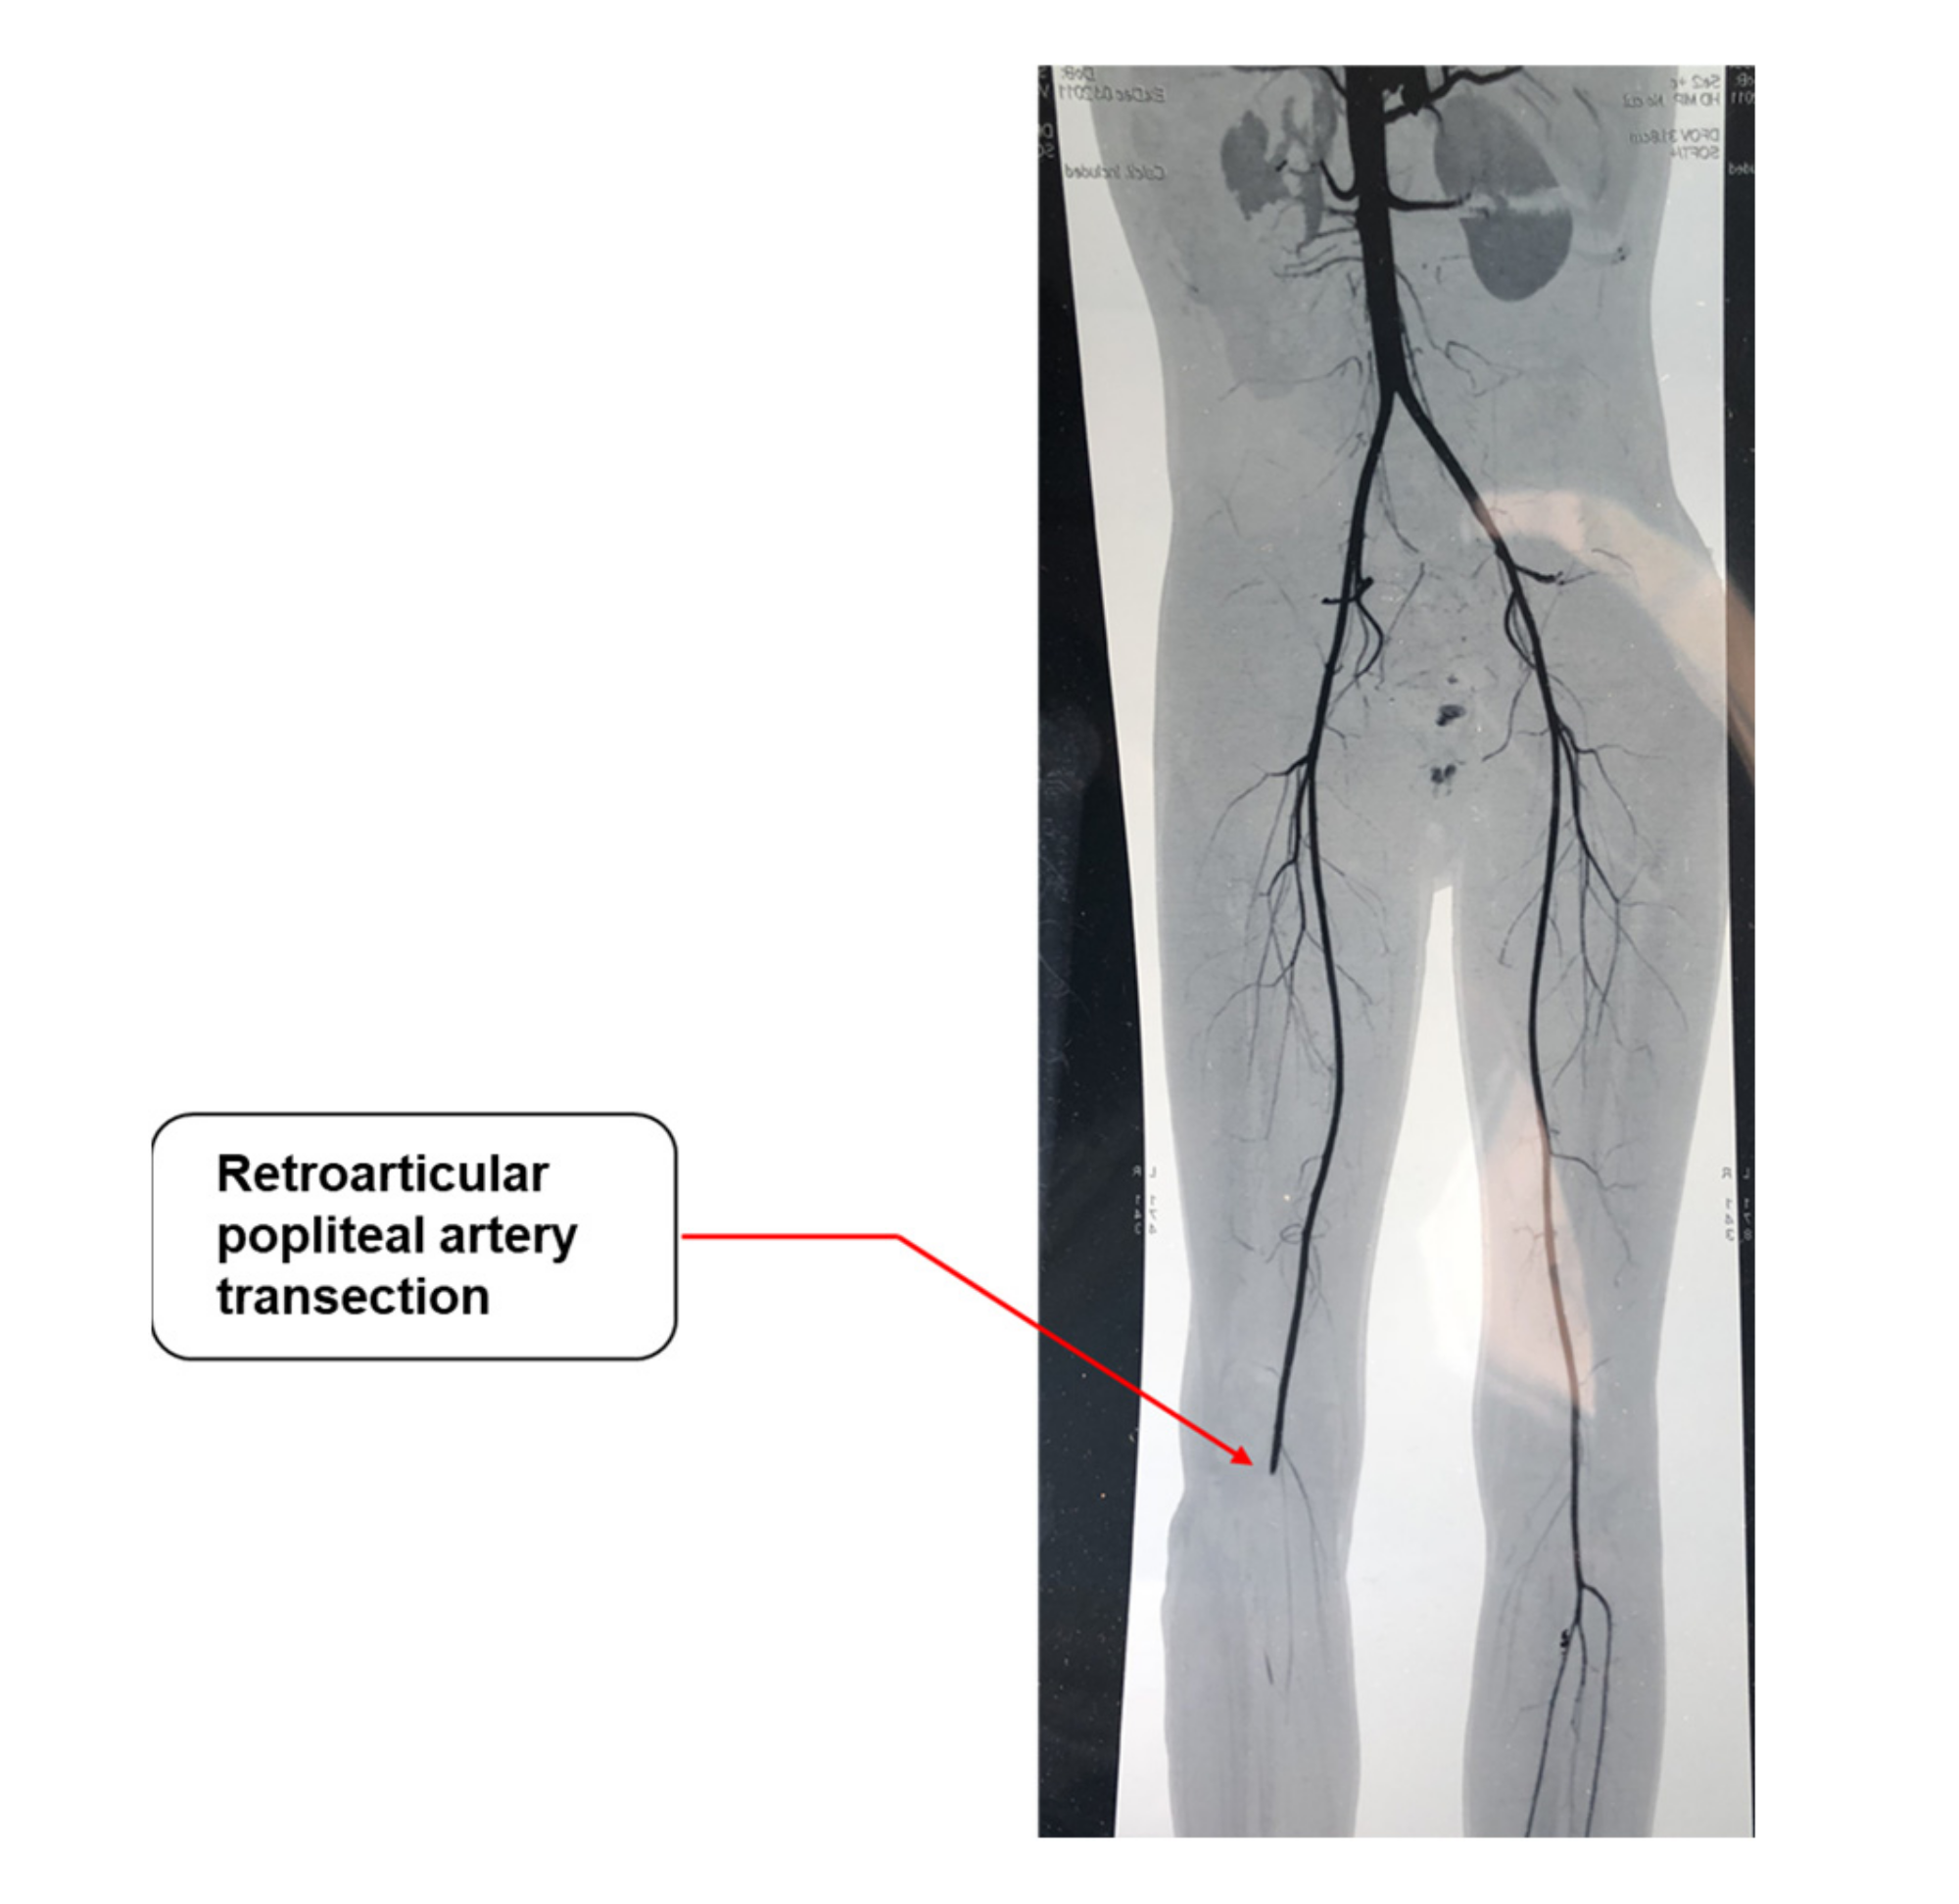

In particular, 29 patients (43.3%) had an isolated arterial injury of the lower limbs and 6 patients (9%) had an isolated venous injury, while 32 patients (47.8%) had a combined arterial and venous injury. Seven patients (10.4%) also had an associated nerve injury, being in six cases a sciatic nerve injury (9%) and in the remaining patient an internal sciatic popliteal nerve injury. The arterial injuries mainly involved the superficial femoral artery (Table 2) and were in most cases either transection (31 cases, 46.2%) (Figure 1) or lacerations (21 cases, 31.3%). Furthermore, the most affected site in case of venous injury was the superficial vein (18 cases, 26.8%), and transections and lacerations were the most represented type of lesions (17 and 19 cases, respectively; Table 2).

Figure 1.

Angio CT showing a right retroarticular popliteal artery transection (red arrow).